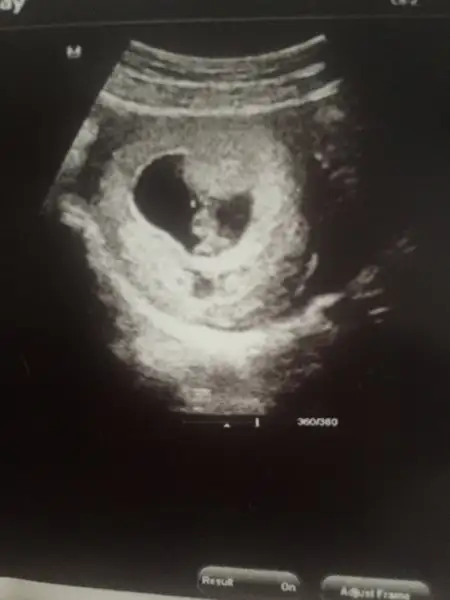

Bu da bir örnektir oğlumun ultrasonu

Eklentiler

• A3D7F61F-1294-4664-A971-15D30CC26C58.webp

13,2 KB · Görüntüleme: 356